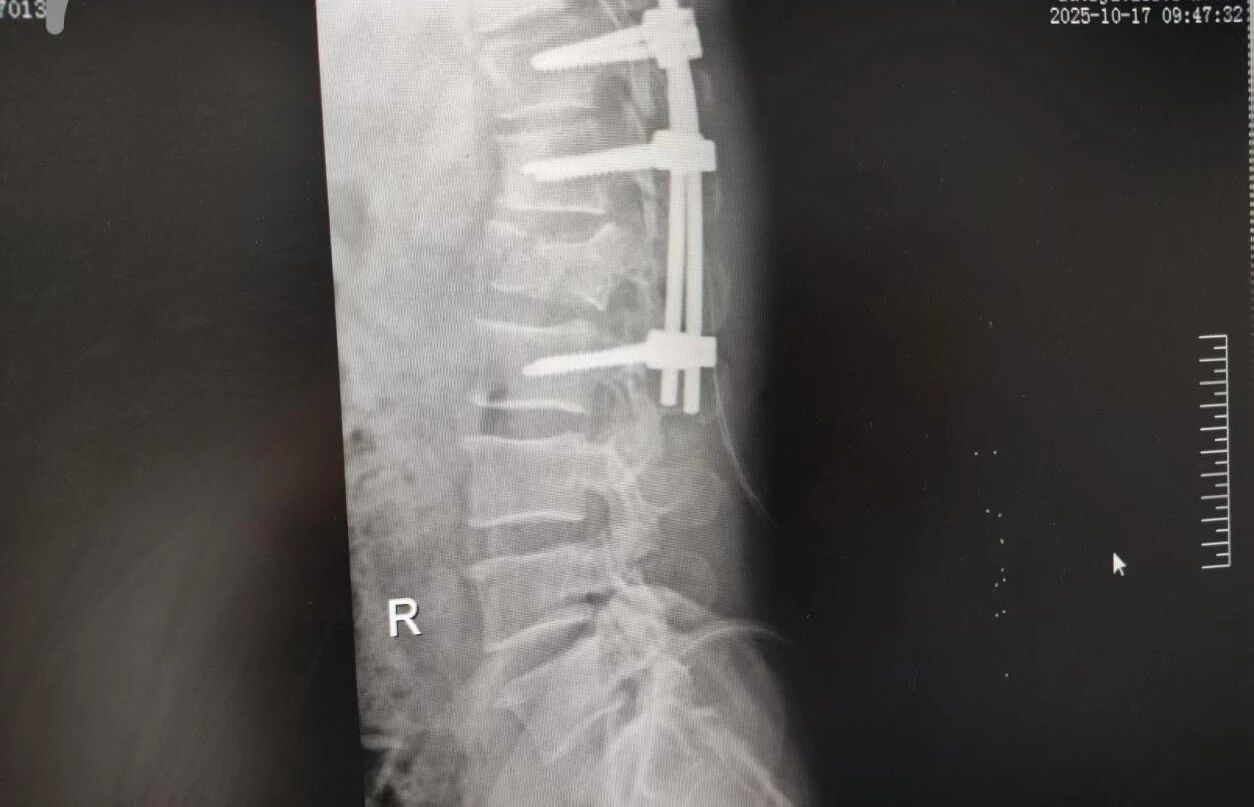

針對腰椎傷情,骨科竇志剛醫(yī)生團(tuán)隊緊急開展腰 1 椎體爆裂性骨折切開復(fù)位內(nèi)固定術(shù) + 椎板切除減壓術(shù)。手術(shù)室、麻醉科無縫銜接開通綠色通道,手術(shù)團(tuán)隊快速就位,術(shù)后患者下肢活動恢復(fù)自如。